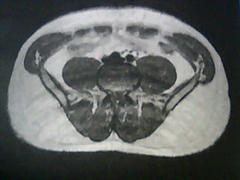

まずは開始前の2006年4月。

このときのMyBodyは以下の通り。

身長 172cm / 体重 80.7kg

体脂肪率 25.3% / 筋肉率 31.4% / BMI 27.2

いや~、見ていると気持ちが悪くなってきます